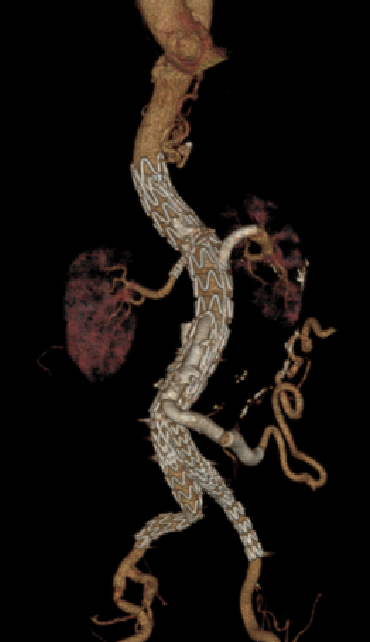

支架稳定性与预防位移

★ 大动脉瘤

分支支架置入后,需预防分支支架从窗口或内脏动脉脱出。动脉瘤形态变化(如主动脉搏动、内漏致瘤体增大)可能导致支架脱出。

预防措施:

内分支或外分支支架应进入主体支架内1cm,进入内脏动脉>2cm。

建议至少置入两个分支支架,以固定主体和分支支架。